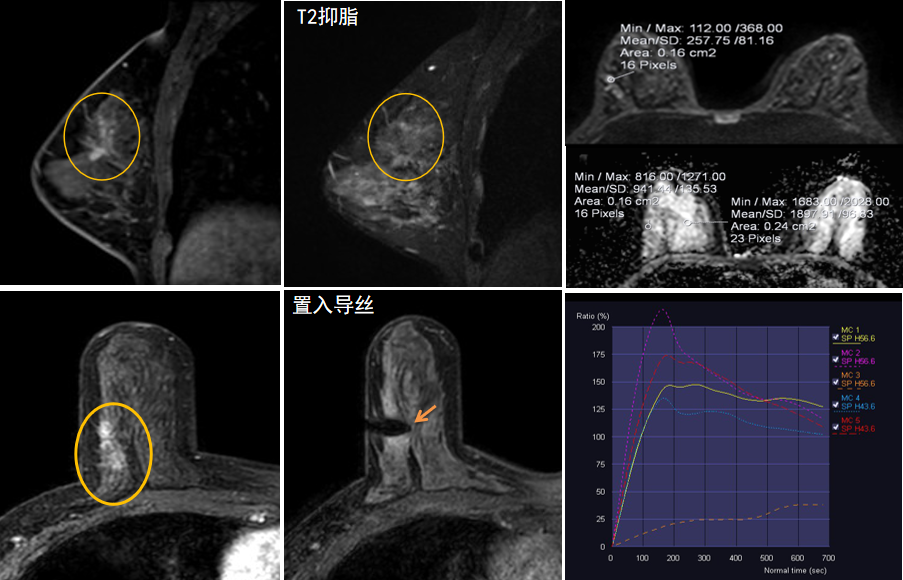

今年45歲的某女士,兩個月前行超聲檢查發(fā)現(xiàn)右乳結(jié)節(jié),乳腺X線攝影檢查提示右乳外上象限局部腺體結(jié)構(gòu)扭曲并簇狀無定形鈣化,為了進一步評估病變性質(zhì)并確定范圍進行了乳腺MR平掃 DWI 增強的檢查,經(jīng)MR評估發(fā)現(xiàn)右乳病變范圍較廣,評估為BI-RADS 4類可疑病變,需要取得病理學(xué)結(jié)果。

只能借助影像學(xué)引導(dǎo),但超聲僅顯示了病變中的小結(jié)節(jié),X線攝影(鉬靶)顯示的病變邊界比較模糊,要想做到精準(zhǔn)完整切除必須借助MR的引導(dǎo),而這一技術(shù)對軟硬件平臺及人員技術(shù)都有很高的要求,因此,多年來一直是我國乳腺病變診療的盲區(qū),經(jīng)常是MR發(fā)現(xiàn)可疑病變但卻無法處理。目前全國僅有少數(shù)幾家醫(yī)院開展了這方面的部分工作。

西安國際醫(yī)學(xué)中心醫(yī)院影像診療中心陳寶瑩主任團隊有著十余年影像引導(dǎo)下乳腺介入診療的經(jīng)驗,借助醫(yī)院高精尖的MR平臺,成為西北首個全面展開MR引導(dǎo)下各項乳腺介入診療技術(shù)的團隊,能夠?qū)Τ暭叭橄賆線無法顯示或顯示不清的病變進行MR引導(dǎo)下的導(dǎo)絲定位、穿刺活檢及真空輔助旋切。

陳寶瑩主任及其帶領(lǐng)的MR介入診療小組詳細(xì)詢問了病情,分析了患者資料,并與患者和臨床醫(yī)生進行了充分溝通,確定于手術(shù)前為患者實施MR引導(dǎo)下的病變穿刺導(dǎo)絲定位和體表范圍確定。手術(shù)前陳寶瑩主任帶領(lǐng)聶品醫(yī)師、馬小偉技師、韓愛萍護士長等MR介入診療小組成員,借助MR高清的圖像顯示和定位系統(tǒng),確定病變范圍,精準(zhǔn)穿刺置入定位導(dǎo)絲,并準(zhǔn)確標(biāo)記出病變體表范圍,整個過程患者無任何不適。在定位導(dǎo)絲和體表范圍標(biāo)記的輔助下,甲乳外科劉曉敏主任精準(zhǔn)切除了病變,解除了患者的后顧之憂。

國內(nèi)外指南均建議40歲以上的女性每年行一次雙乳X線攝影(鉬靶)檢查,以篩查乳腺癌。對于乳腺癌高危人群40歲以前即建議開始乳腺癌篩查,除了進行乳腺X線攝影(鉬靶)篩查外需要補充MR檢查,MR檢查敏感性最高,能夠發(fā)現(xiàn)大量X線攝影和超聲檢查陰性的可疑病變,基于多模態(tài)、多參數(shù)的結(jié)構(gòu)和功能成像的基礎(chǔ)上,MR能夠精準(zhǔn)顯示病變位置、范圍以及病變內(nèi)的活性區(qū)域,MR引導(dǎo)下的介入診療不但解決了僅在MR顯示的病變的處置難題,而且能夠精準(zhǔn)定位活性區(qū)域,保證了定位、活檢及旋切的準(zhǔn)確性。